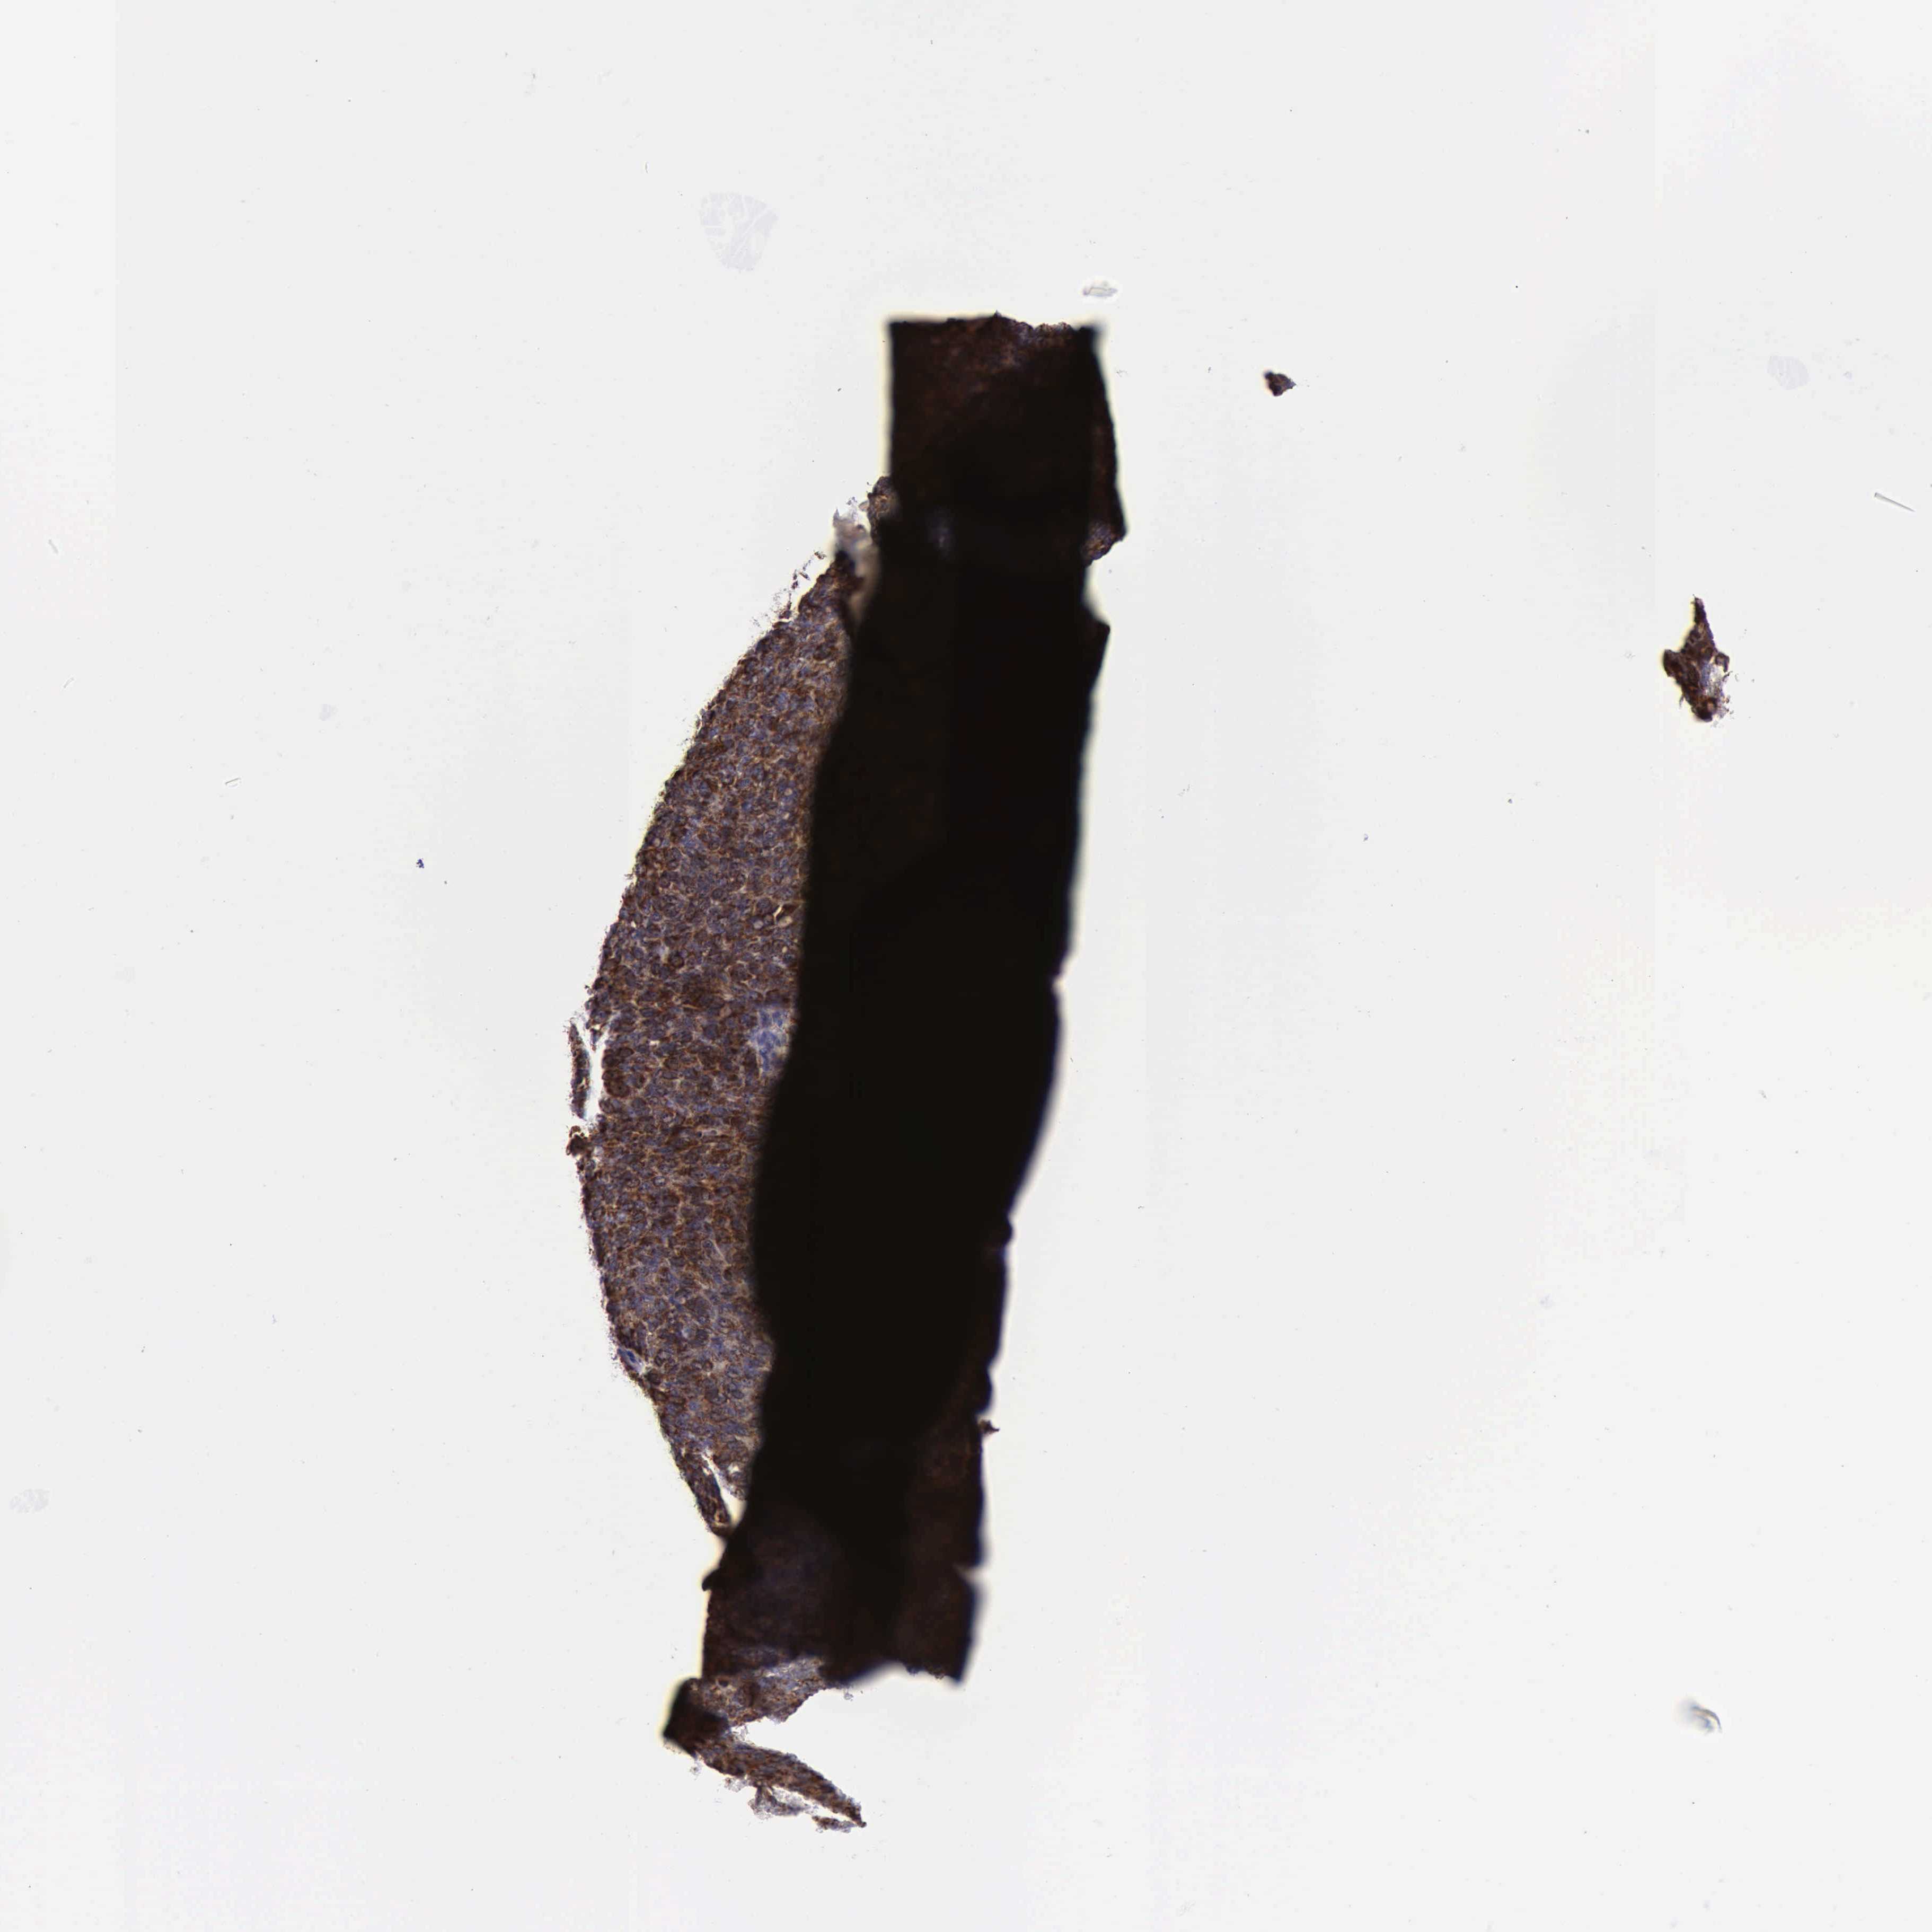

OVARIAN CANCER - Protein expressioni

A mouse-over function shows sample information and annotation data. Click on an image to view it in a full screen mode. Samples can be filtered based on level of antibody staining by selecting one or several of the following categories: high, medium, low and not detected. The assay and annotation is described here.

Note that samples used for immunohistochemistry by the Human Protein Atlas do not correspond to samples in the TCGA dataset.

Antibody stainingi

Antibody staining in the annotated cell types in the current human tissue is reported as not detected, low, medium, or high, based on conventional immunohistochemistry profiling in selected tissues. This score is based on the combination of the staining intensity and fraction of stained cells.

Each image is clickable and will lead to virtual microscopy that enables deeper exploration of all samples and also displays staining intensity scores, fraction scores and subcellular localization as well as patient and tissue information for each sample.

Antibody HPA000994

Antibody CAB008681

Cystadenocarcinoma, mucinous, NOS

Carcinoma, endometroid

Cystadenocarcinoma, serous, NOS

Carcinoma, NOS